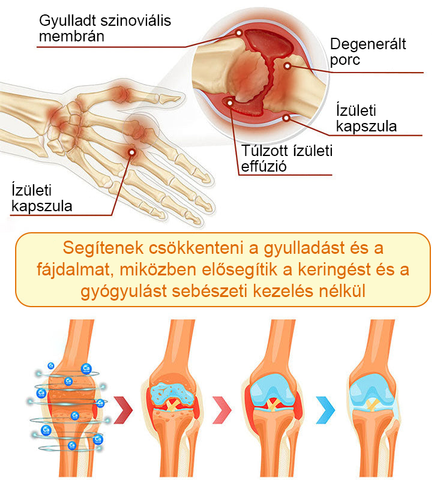

Az ortopédiai betegségek számos tényező miatt fordulhatnak elő, beleértve az életkorral összefüggő degenerációt, túlzott igénybevételt vagy sérülést, genetikát és bizonyos egészségügyi állapotokat, például cukorbetegséget vagy reumás ízületi gyulladást; A rossz testtartás, a helytelen táplálkozás, valamint bizonyos típusú munka vagy sport szintén növelheti az ortopédiai állapot kialakulásának kockázatát.

A reumatoid arthritis (RA) egy krónikus gyulladásos betegség, amely a szinovális hártyát támadó autoimmun reakció következtében gyulladást és károsodást okoz az ízületekben. A reumatoid arthritis ízületi fájdalommal, duzzanattal és merevséggel jár, és általában a kisebb ízületekben, például az ujjakban, csuklókban, térdekben és bokákban fordul elő, de más nagyobb ízületeket is érinthet.

Az osteoarthritis (OA) egy gyakori degeneratív ízületi betegség, amely jellemzően az életkor előrehaladtával romlik, és az ízületi porckopáshoz, valamint degenerációhoz vezet. Ez egy krónikus állapot, amely leggyakrabban a testsúlyt viselő ízületeket érinti, mint például a térdeket, csípőket, gerincet és kezeket. Ahogy a porc fokozatosan elhasználódik, a csontok közötti súrlódás növekedése ízületi fájdalmat, merevséget és mozgáskorlátozottságot okoz.

A statisztikák szerint a világ népességének 35%-a szenved ízületi problémáktól, és minden 5. ember különböző fokú ízületi problémákkal küzd. A mérsékelt esetek közé tartoznak olyan állapotok, mint az arthritis, reumás betegségek és köszvény, melyek tünetei közé tartoznak a fájdalom, merevség, duzzanat, mozgási nehézségek, fáradtság és csökkent mozgástartomány. Súlyosabb esetekben ízületi deformitások, láz és intenzív ízületi fájdalom is kialakulhat, amelyek krónikus fájdalomhoz és fogyatékossághoz vezethetnek. A legsúlyosabb esetekben az ortopédiai betegségek életveszélyes szövődményeket is kiválthatnak.

A TLOPA® Botulinum Toxin & Bee Venom Pain-Relief Bone Healing Cream segít az osteoarthritis, reumatoid arthritis, bursitis, tendinitis, csontritkulás, köszvény, carpalis alagútszindróma, ínszalag rándulások és húzódások, bütykök és teniszkönyök kezelésében.

A TLOPA® krém természetes méhméreg kivonatot tartalmaz, amely hatékonyan javítja az ízületek rugalmasságát. Az aktív összetevő, a "méhméreg peptid" mélyen behatol az ízületekbe, enyhítve a gyulladás okozta merevséget és kényelmetlenséget, segítve az ízületi mozgékonyság visszaállítását. Idővel a méhméreg gyulladáscsökkentő hatásai tovább serkentik a szinoviális folyadék termelését, jobb kenést biztosítva az ízületek számára, csökkentve a súrlódást, és jelentősen javítva az ízületi rugalmasságot 7 napon belül.

A botulinum toxin blokkolja a fájdalomjeleket, míg a méhméreg a bioaktív összetevői révén enyhíti a fájdalmat, így biztosítva a kettős fájdalomcsillapítást. Ezen kívül a méhméreg felgyorsítja a mikrokeringést és a sejtek regenerációját, együttműködve a botulinum toxin izomlazító hatásával, javítva az ízületek rugalmasságát és segítve az ízületi szövetek helyreállítását. Ez a kombináció nemcsak hatékonyan enyhíti az ízületi fájdalmat, hanem erősíti a csontokat, támogatja a hosszú távú csont-egészséget, és segít megelőzni az oszteoporózist és más csontdegeneratív problémákat.

A botulinum toxin egy erősen koncentrált oldat, amely gyorsan felszívódik a bőrön keresztül. Elengedhetetlen az izmok és ízületek egészségéhez, mivel segít az izmok ellazításában, enyhíti az izomgörcsöket, és csökkenti az arthritis által okozott fájdalmat. Emellett a botulinum toxin erős gyulladáscsökkentő tulajdonságokkal rendelkezik, amelyek segítenek csökkenteni az ízületek duzzanatait és gyulladását, javítva ezzel az ízületi mozgékonyságot.

A méhméreg számos aktív összetevőben gazdag, mint például a foszfolipáz A2, peptidek és enzimek, amelyek serkentik a vérkeringést és segítenek enyhíteni az arthritis és izomfájdalmat. A méhméreg természetes gyulladáscsökkentő tulajdonságokkal rendelkezik, csökkentve a gyulladási válaszokat, és enyhíti az ízületek duzzanatát és merevségét. Továbbá, a méhméreg elősegíti a szövetek regenerálódását, helyreállítja az ízületek mozgékonyságát, és javítja az általános mozgás képességét.